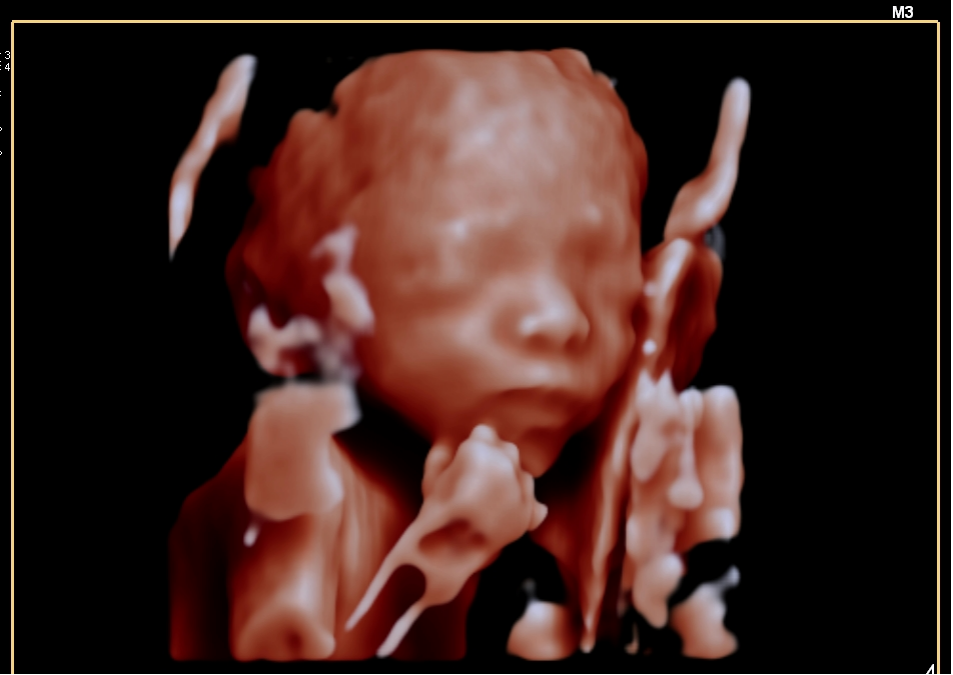

四维彩超就像是给宝宝在子宫里拍的一段 “动态3D电影” 。它能够让准爸爸准妈妈们清晰地看到宝宝在肚子里的实时动态,比如打哈欠、吃手指、微笑、翻身等,为孕期增添了许多惊喜和温情。

四维彩超是系统性产前超声检查的一种高级形式。它通常在孕中期(20-24周左右)进行,医生会利用四维彩超的高清晰度,系统地筛查宝宝是否存在重大的结构畸形,例如:

此时宝宝脂肪还不多,骨骼回声影响小,图像清晰,身体结构也发育到可以筛查的程度。这是进行系统性大排畸的最主要时期。